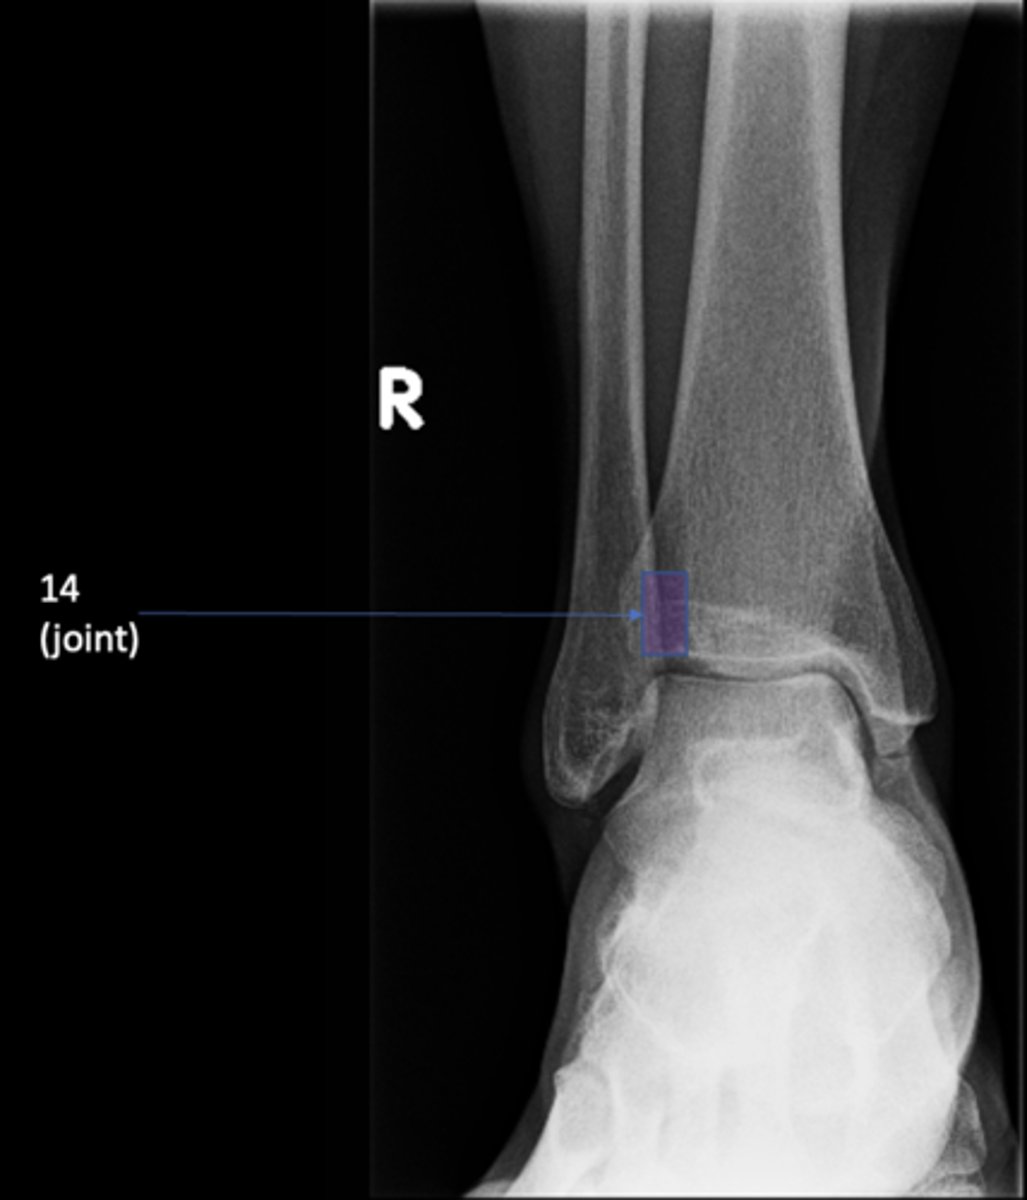

Right posterior superior iliac spine

ID 11

<p>ID 11</p>

12

New cards

Left femoral neck

ID 12